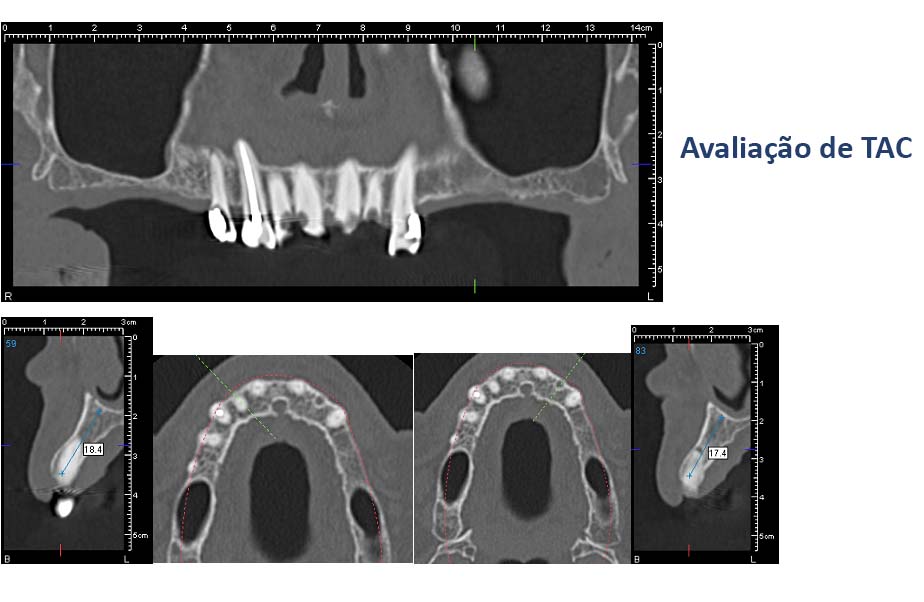

• If necessary additional exames are taken (TAC)

Urgent treatments are executed if necessary as in the case on the left.